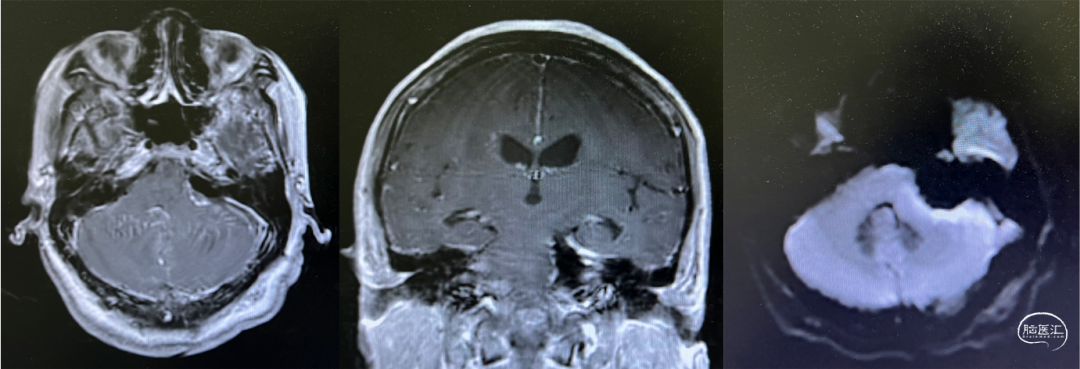

手术时间正值壮族传统节日“三月三”前夕,由冯睿医生主刀、付志为医生为一助,杨芳护士辅助,在无脑压板牵拉的显微操作技术下,充分显露肿瘤,逐步切除,同时利用电生理监测,实时保护神经功能。肿瘤与脑干和颅神经粘连极紧,在操作时多次出现心率下降,需要“抽丝剥茧”般的耐心,才能安全切除。最终,肿瘤达到全切除,颅神经、脑干功能和解剖结构均保存完好,电生理监测确认功能良好。妥善止血后结束手术。神经电生理监测由上海诺诚电气提供技术支持,术中进行了体感诱发电位(SEP)、运动诱发电位(MEP)、三叉神经监测、面神经监测等。手术总时间9小时,显微操作下肿瘤切除时间达6小时。

患者术后在手术室内即复苏、恢复神志,气管插管保留至次日拔除。患者术后第三日开始下床活动,并开始接受床旁康复治疗。磁共振复查提示,肿瘤全切除,脑干无缺血表现。